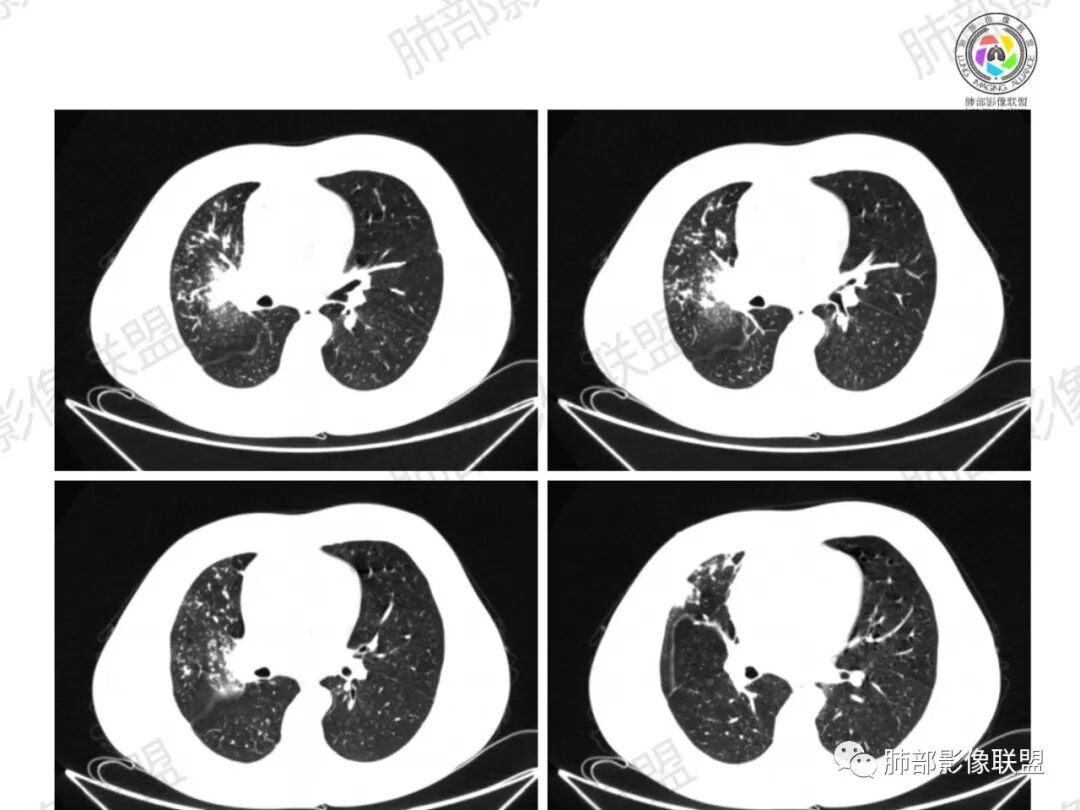

远端有些花花草草

多发树芽,病灶边缘模糊的GGO

怎么看怎么不符合恶性,远端并不是明显的阻塞性炎改变,一是主要表现为树芽和结节,二是未按责任支气管分布。

1、坏死区内寸草不生;2、病灶环形强化;3、远端树芽和结节;4、远端不是阻塞性炎症,而是树芽和结节,右肺上叶前后段都有,后段为主,而堵塞的支气管应该是前段;这些树芽的位置不是堵塞支气管的责任区;5、支气管不是突然截断堵塞,而是逐渐狭窄;6、纵隔淋巴结是椭圆形增大,内有坏死,不是肿瘤的圆形饱满;7、支气管周围粘液样坏死,符合仙人掌结核改变;

3、阻塞性炎症:这个病例远端的散在病灶分布与责任支气管不符,所以不是阻塞性炎症,应该是树芽;

所以,这个病例应先考虑炎性病变,以结核可能性大。慢性非特异性炎症伴脓肿形成,也可以这样的影像改变,但解释不了周围的树芽和结节。